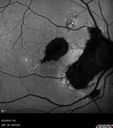

Macular Telangiectasis and Vision loss following vitrectomy with membrane peel379 views76 year old man with MacTel who had membrane peel in the right eye 10 years ago with permanent vision loss.

VA OD: sc20/200-4 and VA OS: sc20/25-1